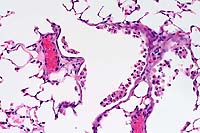

- Case 9-2 . Kidney. Proximal tubule epithelium (right

center) is swollen and vacuolated with nuclear pyknosis (degeneration

& necrosis). Some distal tubules contain homogenous light

pink material (hyaline cast, lower right) and others are filled

with hemoglobin casts (left). Some tubular lumens contain an

admixture of pink protein, sloughed epithelial cells, and neutrophils.

Occassional tubular epithelium has increased basophilia (hyperplasia).

The interstitium is expanded by edema and contains low to moderate

numbers of lymphocytes and macrophages.